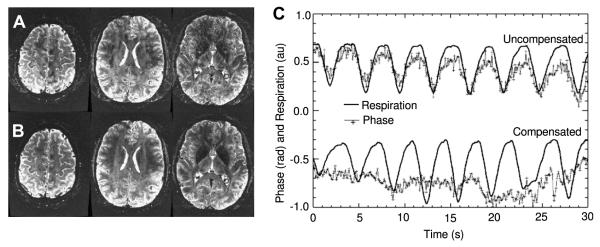

The literature has documented homogeneous and spatially varying B0 fluctuations resulting from patient respiration [71,72]. While these effects are typically low in amplitude, at B0 field strengths over 3T such physiologically induced macroscopic B0 perturbations can become problematic in highly phase-sensitive experiments.

Van Gelderen et al. [73] have developed a dynamic shimming system capable of compensating such effects in real-time. This compensation mechanism requires the introduction of two unique components to dynamic shim updating. First, the effects of respiration on the B0 (or phase-accumulation) field distribution must be measured. Second, the shim amplifiers must be triggered to update shims during scans using active measurements of the patient’s respiratory cycles. Using typical hardware available for cardiacgated acquisitions, Van Gelderen et al. calibrated and implemented such a system capable of actively compensating all zeroth through second-order respiration-induced field changes.

Fig. 16 presents the improvements in ghost reduction by compensating respiration-induced phase changes. (A) Shows images acquired without compensation. (B) Shows the images collected with temporal DSU compensation. The ghosting improvements are best visualized outside the brain region. However, ghosting does significantly impact signal intensities inside the brain as well. (C) Displays the effects of respiration on measured phase within a single imaging voxel. Both the measured phase and respiration are temporally tracked. Without temporal DSU compensation, there is a clear tracking of phase with the respiratory cycle. When temporal DSU is applied, the compensated phase has a much smaller dependence on the respiratory cycle. Though the phase modulation induced by respiration is low in amplitude, these changes can effect image ghosting. A conventional phase-correction strategy implemented in EPI uses an acquired reference scan without phase-encoding blips to measure and remove unwanted phase variations in a post-processing step. Such a correction mechanism requires extremely precise assessment of phase accumulation resulting from gradient asymmetries and induced eddy-currents. The extraneous phase modulations induced by respiration (and not accounted for in a reference-scan based correction) are easily large enough to degrade the success of such correction mechanisms.

Fig. 16.

Axial sliced gradient echo images (B0 = 7T, TE 40 ms, TR = 500 ms) without (A) and with (B) respiration-compensated dynamic shimming. (C) Temporal plots of phase measured in a single imaging voxel and respiration. Without temporal DSU, there is a clear tracking of phase with the respiratory cycle. When temporal DSU is applied, the compensated phase has a much smaller dependence on the respiratory cycle. Results courtesy of Dr. Peter van Gelderen.

Given that the incremental changes in second-order shims are very low in amplitude, this application of dynamic shim updating does not necessitate the use of higher-order shim pre-emphasis.

5.1.4. Real-time compensation of motion-induced B0 fluctuations

When a patient moves within the B0 field, the sample-induced B0 distribution will not move in a one-to-one fashion with the patient motion. Therefore, another application of DSU in the temporal regime is the compensation of shim changes induced by patient motion.

Ward et al. [74] have demonstrated that use of navigator projection field-map measurements can be applied to update linear shim terms in real-time during an EPI timeseries experiment. Patient motion can cause particularly significant temporal B0 perturbations when motion occurs in the coronal or sagittal planes. Using the field-map navigators, Ward et al. were able to insert compensating blips in the linear field gradients to compensate accumulated phase in EPI experiments. These blips could be updated on a per-image basis during timeseries acquisitions without significantly impacting on temporal resolution.

In conclusion, for multi-volume MR acquisitions DSU can enable significantly improved utility of available RT shims. Tremendous improvements in multi-voxel spectroscopy have been demonstrated with DSU, particularly when compared to static RT shimming. Temporal DSU has also been demonstrated to be extremely useful for compensation of low-order field-changes induced by patient respiration and patient motion.

Improvements in multi-slice imaging (both spectroscopic and echo-planar) are significant when DSU is utilized. However, in these investigations it is clear that even when optimized over whole individual slices, available room temperature shims remain unable to completely compensate unwanted inhomogeneity.

5.2. Alternative shimming approaches

Since there are significant physical limitations in extending RT shim technology to higher-orders, further improvements in whole-brain shimming at high static magnetic field strengths will necessarily move away from conventional mechanisms. In recent years, a number of alternative shimming measures have been proposed and demonstrated.

5.2.1. Local active shimming

Hsu et al. [75] have shown that the human oral cavity can be useful for the placement of local electromagnetic shim coils. In this approach, three independently adjustable current loops were combined to form an array of loops making different angles with respect to the axis. The shim fields produced by localized current loops are roughly dipolar in nature. However, when optimized independently, they can be combined to shape a net local-shim field on a subject-specific basis. In reference [75], a subject specific optimization procedure for use with the local shim system is also described and demonstrated.

Fig. 17 displays improvements in gained with the local shim system at 1.5T. (A) Provides a photograph of the shim assembly and its placement in the mouth relative to the brain. (B) Presents optimally shimmed field maps without (top) and with (bottom) use of the intra-oral shim assembly. (C) Demonstrates improvements in signal recovery near the sinus cavities when the local shim is utilized. Significant overall homogeneity improvements with use of the local shim coils are clear in all displayed slices.

Fig. 17.

(A) Image and anatomic location of intra-oral local active shims. (B) Field-map results of optimized local active shim use. (C) Signal-recovery in gradient-echo imaging (TE = 40 ms, 5 mm slices) with the local shim assembly. B0 = 1.5T Reproduced from [75] with permission of Wiley-Liss, Inc., a subsidiary of John Wiley and Sons, Inc.

Ohmic heating is a potential concern of this approach. While the experiments conducted at 1.5T required shim currents that did not produce appreciable temperature changes, the increased currents needed to accurately shim at 3 or 7T may need to be carefully considered. Patient comfort is also a crucial factor in the use of any oral shimming device. Wong et al. [76] have also shown initial results on an external local electromagnetic shimming approach, although such an approach has yet to be published in detailed fashion.

5.2.2. Subject-specific passive shimming

Passive shimming is an approach whereby magnetic materials are strategically placed around a sample to cancel unwanted inhomogeneity. This shimming methodology uses the induced magnetic field of the shimming material to compensate unwanted B0 heterogeneity.

Mathematically, this type of shimming is accomplished by developing the passive shim field (BPS) introduced in Eq. (45). BPS is then used in combination with the RT shim field to satisfy the shimming condition given by Eq. (46). Paramagnetic, diamagnetic, and ferromagnetic materials can all be utilized for passive shimming.

5.2.3. Intra-oral diamagnetic passive shimming

The inhomogeneity distribution generated by the sinus cavities in the human brain is roughly dipolar in shape. This general distribution geometry is created by the difference in magnetic susceptibility of air in the sinus cavities and the surrounding biological tissue. The result is a net paramagnetic dipolar effect (i.e. the field that would be generated by placement of a localized paramagnetic material in the B0 field), where the pure dipolar result is given by Eq. (19) for the field-induced external to a sphere of magnetic material. Of course, this is a very crude analysis of the problem. The local variation of sinus cavity geometries distorts this actual field geometry from that of an analytic finite dipole. However, the general lobe structure of a paramagnetic dipole can be observed near the sinus cavities of most human subjects.

Wilson et al. [77] sought to reduce the effects of this roughly dipolar field distribution by placing a highly diamagnetic material in the mouth of patients. The oral cavity is located directly underneath the sinus cavity in the direction. Therefore, the lobe of a dipole generated by placement of highly diamagnetic material in the mouth can be useful in reducing the effects of the paramagnetic dipole induced by the sinus cavities. As a diamagnetic material, Wilson et al. utilized pyrolytic-graphite (PG), which has a highly anisotropic magnetic susceptibility tensor with components χPG,⊥≈−450 ppm perpendicular to the basal plane and χPG,∥≈−85 ppm [78] parallel to the basal pane.

The construction of the diamagnetic mouth shims required fabrication of a dental mold for each patient. Such dental molds are needed to hold the graphite in place because utilization of PG’s strong susceptibility component requires positioning of the graphite in an energetically maximal configuration with respect to the B0 field. A block of pyrolytic graphite prefers to be oriented with its weak magnetic susceptibility dimension parallel to B0 and will always try to move to this preferred orientation. The forces from this anisotropic susceptibility effect are significant (though not dangerous) at 3T. It is also important to ensure that PG shim components do not move during an imaging session, as such movement could significantly compromise image quality.

An optimization procedure was developed to determine a patient-specific pyrolytic graphite oral insert from a pre-established basis set of shims [79]. This is an important consideration for human passive shimming applications, where variation across subjects is certain and significant.

Fig. 18 presents field-mapping results of intra-oral diamagnetic shimming at 3T. (A) A photograph of the graphite shim assembly. The carefully stacked construction is an important consideration due to the anisotropic magnetic susceptibility of pyrolytic graphite. Axial field maps in the top row of (B) show homogeneity attainable with available RT shim technology. The now familiar region of B0 inhomogeneity near the sinus cavity is clearly visible. Maps in the bottom row of (B) demonstrate significant improvements in homogeneity near the sinus cavity with use of the diamagnetic intra-oral shim.

Fig. 18.

(A) Photograph of the highly-ordered pyrolytic graphite shim assembly. (B) Axial magnetic field maps without and with use of an intra-oral diamagnetic passive shim. Reproduced from [77] with permission of Wiley-Liss, Inc., a subsidiary of John Wiley and Sons, Inc.

While this approach does make improvements in a number of slices, it is clear that significant inhomogeneity remains after passive shimming. Primarily in the lower slices, prominent inhomogeneity remains near the auditory and sinus cavities. Though Wilson et al. also attempted using diamagnetic ear shim-plugs, no significant homogeneity improvements were observed with their use.

5.2.4. Subject-specific ferroshimming

As previously discussed, ferroshimming is a conventional approach to shimming of the subject-independent B0 distribution within a magnet. However, there have also been approaches to ferroshimming subject-specific field distributions.

Standard copy-toner has a magnetic susceptibility close to nickel, which is ferromagnetic. Jesmanowicz et al. [80] sought to optimize printed distributions of copy toner on sheets of paper which were subsequently rolled to form ferroshim inserts. With the idea that the shims could be printed on a subject-specific basis, such a ferroshimming approach was intended to allow for robust higher-order global shimming on the human brain. This approach required the decomposition of dipolar shaped induction fields from a basis set of shim elements into spherical harmonics. Furthermore, it was assumed that the dipole moment for each induction field scales linearly with the element thickness. A least-squares linear programming solution then utilized these analytic relations of dipolar ferroshims to determine the optimum printout shim designs on a subject-specific basis. While preliminary work on this approach has been published [80], there have been no follow-up studies or rigorous assessments of the technique’s utility.

Juchem et al. [81] also developed a method of generating second-order spherical harmonic terms on a subject-specific basis using ferroshim materials. In this work, it was shown that high-amplitude second-order shim terms could be optimally produced from only a few carefully placed ferroshim (Ni–Fe permalloy) segments. Using a calibrated scaling process and optimization over targeted spherical harmonic coefficients calculated using the FASTMAP algorithm, it was demonstrated that high-amplitude second-order terms could be optimized to robustly shim the visual cortex of macaque monkeys on a subject specific basis. The primary motivation of these developments were to allow high-amplitude subject-specific second-order shimming in a high-field system (7T) equipped with relatively weak RT active shims (designed for 3T). However, the work does demonstrate that robust subject-specific passive shimming is feasible and can enhance the capabilities of available RT shims.

While all of the subject-specific passive shimming approaches discussed thus far utilize only one material for passive shimming, it has also been demonstrated that passive shimming can be accomplished using combinations of diamagnetic and paramagnetic shim elements.

5.2.5. Subject-specific diamagnetic and paramagnetic passive shimming

Given a user-defined grid for placement of shim materials, a calculation procedure to determine optimal stacks of both diamagnetic and paramagnetic shim elements at each position in the grid has been developed [82]. The accuracy of this method hinges on three approximations in the nature of the magnetic fields induced by the shim materials.

The induction fields from shim elements (or stacks of elements) at separate shim grid positions add in linear superposition.

The amplitude and shape of an induction field from a shim element is dominated by its own susceptibility and is trivially perturbed by other nearby materials with much smaller magnetic susceptibilities.

The geometric distribution of an element’s induction field does not change when elements are stacked together in a limited fashion.

The physical basis of approximations 1 and 2 is essentially the same first-order approximation to the general magnetostatic solution that has been utilized repeatedly throughout this review. Empirical measurements verifying approximations 1–3, along with the details of the following methods and results are presented in detail within reference [82].

Utilizing these approximations and given a targeted inhomogeneity distribution, the shim composition calculation can be reduced to a linear problem rapidly soluble with readily available optimization algorithms. This allows for real-time and active-adjustment of the passive shim assembly.

Due to its high surface to volume ratio, the mouse brain possesses some of the most severe magnetic field inhomogeneity found in vivo. Despite this limitation, the demand for mouse investigations in NMR has been rapidly increasing-particularly in the phenotyping of transgenic mice. Therefore, the first demonstrations of combined diamagnetic and paramagnetic passive shimming were performed on the mouse brain at 9.4T [82,83]. These shim systems used diamagnetic bismuth (Bi), paramagnetic zirconium (Zr), and paramagnetic niobium (Nb) metals as shim materials. Schenck [33] reports absolute susceptibility values for the three metals as −164, +92, and +237 ppm, respectively. Computed shim material distributions were realized on acrylic cone-shaped shim formers surrounding the mouse brains.

Fig. 19 provides field mapping diagnostics of the prototyped passive shim system in three coronal slices positioned throughout the mouse brain at 9.4T. Inhomogeneity is significantly reduced in moving from the unshimmed to the passively shimmed maps for all slices. The second-order actively shimmed map represents the best shimming alternative using previously existing technology on the utilized imaging system. Noticeable improvement is visually recognizable when comparing the passively shimmed field map to the room-temperature shimmed (RTS) field map. The required coefficients for the added inclusion of third order shims were roughly 10 times the available shim strengths, which is a common problem for RT shimming beyond second-order terms in the mouse brain at 9.4T [84].

Fig. 19.

(A) Photograph of a combined diamagnetic and paramagnetic shim assembly on the mouse brain. (B) Shim former radii and shim element positioning for two prototyped constructions. (C) Field map (B0 = 9.4T) images demonstrating the utility of the passive shim system over three coronal slices in the mouse brain, spanning a range of 3 mm. Residual field maps are shown for no shimming, active RT shimming, passive shimming with prototypes of R0 = 3.0 cm and R0 = 2.5 cm. Reproduced from [82] with permission of Elsevier.

The dramatic performance improvements of the reduced-radius shim assembly demonstrate a crucial consideration in this passive shimming approach. Compensation of higher-orders inhomogeneity with the presented shimming system benefits from the availability of steep field gradients at each grid position. Therefore, the higher-order compensating capability of the system is highly-dependent on the proximity of the shim grid to the shim volume.

The advantages of the two material passive shimming over both one metal passive shimming and low-order spherical harmonic optimization are presented in Fig. 20. Computational residual field maps from a slice near the auditory cavities are shown for both one and two metal implementations of the shim system. A field map from a computational third order room temperature shim optimized over the entire brain is also presented. The improved higher order shimming capacity of the two metal optimization over both the one-metal (Zr) and ideal third-order RT shim (using shim strengths well outside the specifications of state-of-the-art shim systems) is visually recognizable, particularly near the sinus and auditory cavities. The one-metal computation was also carried out with bismuth, which gave even poorer results.

Fig. 20.

Reduction of higher-order inhomogeneity by active and passive shimming. Residual magnetic field maps (B0 = 9.4T) near auditory air cavities are presented using (A) no shim, (B) a computational third-order RTS, (C) computational one-material (zirconium) passive shim, and (D) computational two-material passive shim. Reproduced from [82] with permission of Elsevier.

The inability of the presented passive shim system to effectively shim with one material is due to two considerations. First, the shim former geometry necessarily deviates significantly from an infinite cylindrical shape (in order to maximize proximity of the shim elements to the shim ROI). Infinite cylindrical former geometries are an assumption relied upon in other ferroshim approaches [80] to effectively generate positive and negative magnetic dipole moments with a single magnetic material. Second, the limited stack heights required to stay within the linear optimization regime restrict the efficacy of a single shim material to compensate the specified magnetic field geometries.

A significant consideration in the use of metallic passive shims is that of RF penetration and heating. Using discrete arrays of shim elements instead of continuous sheets of metal can help in alleviating this concern. Furthermore, the metals utilized in the diamagnetic/paramagnetic mouse shim system have relatively low conductivities at room temperature. B1 mapping experiments on the mouse passive shim system showed no significant RF variation with and without the use of the shim assembly. Temperature measurements were also taken directly from the shim elements to address RF heating concerns. No measurable temperature change was recorded after running a standard gradient-echo imaging sequence for 45 min with the shim system.

5.3. Future directions

5.3.1. Volume-parcellated DSU

The DSU applications demonstrated in Section 5.1 updated RT shim settings on an individual voxel (spectroscopy) or whole-slice (imaging) basis. For application to whole-brain imaging, optimization of shim settings on a whole-slice basis is the simplest and most obvious dynamic shimming pathway. However, it has been shown by Poole et al. [85] that far greater improvements can be gained with more freedom in the geometry of shim-optimized sub-volumes.

For an initial 3D field-map grid of 96 × 96 × 96 pixels, Poole et al. computationally examined whole-brain homogeneity after zeroth through second-order dynamic shimming of various volume parcellation schemes. Such parcellation schemes ranged from a single optimization volume of 96 × 96 × 96 pixels (global static shimming) to dynamic optimizations of 96 × 96 × 1 (whole-slice shimming), 96 × 12 × 8 (columnar parcellation), and 24 × 24 × 16 pixel volumes. While typical zeroth through second-order shim strengths are adequate for whole-brain or whole-slice shimming, optimization over reduced volumes can require shim currents outside of available constructions. Therefore, Poole et al. constrained their computational DSU optimization based on the efficiencies of a previously designed insertable head shim set [46].

Fig. 21 presents sample results of this investigation. Anatomic images (A) and magnetic field maps for B0 = 3T are shown for three orthogonal imaging planes using (B) static global shimming (96 × 96 × 96), whole-slice shimming (C) (96 × 96 × 1), and volume-parcellated shimming (D) (48 × 24 × 8). Residual field maps were calculated using the methods described in [85].

Fig. 21.

Computed effects of volume parcellation on the global-homogenization capabilities of DSU. Anatomic images (A) and magnetic field maps at B0 = 3T are shown for three imaging planes using (B) static global shimming (96 × 96 × 96), whole-slice shimming (C) (96 × 96 × 1), and volume-parcellated shimming (D) (48 × 24 × 8). Results courtesy of Dr. Michael Poole.

The results of this computational investigation clearly demonstrate the potential benefits of using volume parcellation in lieu of whole-slice shim optimization. The gains in global homogeneity through volume parcellation over whole-slice optimization are most noticeable in the near vicinity of the auditory and sinus cavities.

Any volume-parcellated DSU application will require an imaging sequence which is compatible with the dynamic shimming principle and possesses excitation and acquisition strategies that do not introduce extensive time penalties or reductions of SNR [85]. No currently existing imaging sequences satisfy such requirements. However, the investigations by Poole et al. show that if such a sequence could be developed, when combined with DSU, the improvements in whole-brain B0 homogeneity could be significant. Future work in this line of investigation will be focused on developing such unconventional imaging strategies.

5.3.2. Advanced passive shimming of the human brain

The human brain poses a significantly more challenging passive-shimming problem than the mouse brain for two primary reasons. First, unlike the mouse brain, most of the residual inhomogeneity in the human brain is significantly distanced from possible external shim elements. The significantly improved results of the mouse shim with only a slightly reduced shim-former diameter highlights this consideration. Second, residual targeted inhomogeneity in the human brain is highly localized. The aforementioned intra-oral diamagnetic passive shimming approach addressed this concern by placing shim elements in patients mouths. Despite the improvements gained through this approach, a more patient-friendly and freely-optimizable passive-shimming system comprised of externally located shim elements would be highly desirable. Preliminary results of combined diamagnetic and paramagnetic passive shimming on the human brain are presented here [86]. In this approach, localized diamagnetic and paramagnetic material distributions are used to effectively ‘shape’ local compensating fields and acutely target residual inhomogeneity. When such local passive shims are optimally positioned and used in combination with low-order RT shims, it is shown that residual inhomogeneity is significantly reduced compared to that after stand-alone RT shimming.

Shims were constructed of diamagnetic bismuth and paramagnetic niobium metals. Pyrolytic graphite is the only material known to be more diamagnetic than bismuth and could be used to replace bismuth in any future implementations (though the modest forces from its susceptibility anisotropy would need to be considered).

Since residual inhomogeneity in the human brain is highly localized to the sinus and auditory cavities, shim fields shaped to selectively target these regions while minimizing any adverse effects on other areas of the brain. Fig. 22 presents illustrations of auditory (A) and sinus (B) shims empirically constructed using the described shaping principles. (C) Displays and illustration of their construction relative to a human head and (D) presents a photograph of the final shim elements and their RF-coil fixation apparatus. Note that none of the shim elements are required to touch patients.

Fig. 22.

(A) Individual elements in sinus shim construction, (B) auditory shim construction (C) illustration showing full shim system, and (D) photographs of the shim construction.

Fig. 23 presents a demonstration of the principles utilized in the shaping procedure. (A) A sagittal anatomic gradient-echo MRI of the human brain. (B) Displays the residual B0 field in the human brain after second-order RT shim optimization, while (C) provides the B0 distribution after external passive shimming using only the bismuth component of the local sinus shim. Finally, (D) displays the residual B0 field after external passive shimming using the combined bismuth and niobium passive shim. Passive shim induction fields were computed using Eq. (44) while the in vivo inhomogeneity was measured using magnetic field maps.

Fig. 23.

(A) sagittal anatomic gradient-echo MRI acquisition, (B) residual B0 inhomogeneity in the brain after whole-brain optimized first and second order RT shimming at B0 = 4T, (C) computed induction field and residual inhomogeneity using a local sinus passive shim as described in Fig. 22 without use of niobium, and (D) with use of niobium. Arrows indicate regions where unwanted effects are introduced by the non-shaped shim.

When compared to the residual inhomogeneity map of the human brain after first and second order RT shims (B), it is clear that the lobe induced by either shim (C or D) would be useful in reducing residual inhomogeneity in the inferior frontal cortex of the brain. However, the bismuth-only shim (C) clearly introduces significant unwanted inhomogeneity to other regions in the frontal lobe of the brain (indicated with arrows). With the addition of niobium shaping elements, the lobe of this added dipole (inverted in sign relative to the lobe of the bismuth block) exacerbates and effectively pushes the lobe of the field induced by the bismuth block towards the positive direction. Furthermore, the lobe of the added niobium cancels the portion of the bismuth’s lobe which previously (C) had introduced unwanted effects in the superior frontal lobe of the brain. As depicted in (D), the resulting shim field selectively targets the inferior frontal cortex of the brain.

Fig. 24 presents residual inhomogeneity field-maps under second-order RT shim settings (B) and combined RT-passive shim settings (C) at 4T. Maps from three slices near the sinus and auditory cavities are presented. Improvements in residual homogeneity near the sinus and auditory cavities are clear in these maps. The field maps qualitatively demonstrate that while the constructed shim system cannot perfectly compensate unwanted inhomogeneity, it does make obvious improvements without significantly introducing additional inhomogeneity.

Fig. 24.

Field map assessment of passive-shim improvement over three axial slices (1–3) at B0 = 4T. (A) Gradient echo MRI, (B) residual inhomogeneity after zeroth through second order RT shimming, and (C) residual inhomogeneity after local passive shimming and zeroth through second-order RT shimming.

Gradient-echo images were also collected with TE = 35 ms. This is representative of TE values utilized in developing contrast in BOLD imaging at 4T. Signal recovery in these long echo-time gradient-echo images is presented Fig. 25. Signal recovery in this slice is most noticeable near both the auditory and sinus cavities.

Fig. 25.

Gradient-echo images (B0 = 4T, TE = 35 ms, slice-thickness = 5 mm, oblique angle = 20°, 128 × 128 pixels over 24 cm × 19 cm) collected without (A) and with (B) local passive shims.

Though these results demonstrate the possibility and utility of using external localized diamagnetic and paramagnetic passive shims for global shimming of the human brain, significant further investigation is required. To reach higher levels of inhomogeneity compensation, the external passive shim system could be combined with other advanced shimming approaches. For instance, Fig. 26 shows field-mapping results of combined zeroth-through second-order whole-slice optimized DSU and diamagnetic/paramagnetic passive shimming of the human brain at 4T.

Fig. 26.

Field-mapping results with utility of combined DSU and passive shimming. Axial MRI images of three slices near the auditory and sinus cavities show the position of field map traces. Residual inhomogeneity after (A) zeroth through second-order RT shimming, (B) RT and DSU shimming, (C) RT and passive shimming, and (D) RT, DSU, and passive shimming. (D) Field-map traces as indicated in MRI (A). B0 = 4T. (For interpretation of color mentioned in this figure the reader is referred to the web version of the article.)

Compared to DSU optimized over whole slices (C), it is clear that passive-shimming (D) can offer significantly more global homogenizing capability. However, when used in combination, (E) shows that DSU can be used to effectively ‘clean up’ after passive shimming to further improve inhomogeneity. More robust passive shimming will likely benefit significantly from DSU assistance. Even greater improvements and robustness to subject variations could potentially be made with the introduction of local shim coils to effectively ‘tune’ the passive shim field on a subject-specific basis.

6. Conclusion

B0 shimming remains an active field of technological development. Sections 2–4 have highlighted some of the primary considerations involved in such development. Utilizing the founding principles of magnetostatic physics, shim coil design, magnetic field mapping, and automated shim optimization, Section 5 presented the remaining challenges posed by B0 shimming of the brain. Advanced shim optimization methods addressing these challenges were further presented in Sections 5.2 and 5.3. Technological developments such as dynamic shim updating, local shim coil application, and subject-specific passive shimming were shown to hold potential for improved B0 homogeneity throughout the brain. These advancements have shown significant progress in reducing the negative consequences of B0 heterogeneity. Investigations will inevitably continue into furthering these advanced shimming capabilities and rendering them viable for general application.

Acknowledgments

The authors would like to thank Dr. Jason Hsu, Dr. Gary Glover, Dr. Peter Jezzard, Dr. Peter van Gelderen, Dr. Michael Poole, and Dr. Richard Bowtell for contributing their results to this review. Further gratitude goes to Terence Nixon, Scott McIntyre, Peter Brown and Dr. Laura Sacolick for their assistance in developing and implementing aspects of the technology presented in this review. Previously unpublished results contained in this review were funded by NIH Grants R21-CA118503 and R01-EB000473.

Glossary

- Active shimming

B0 shimming whereby sets of electromagnetic coils are used to shim in a subject-specific fashion

- Diamagnetic materials

Materials that induce magnetic fields which oppose applied fields (negative magnetic susceptibility)

- DSU: dynamic shim updating

Technique whereby RT shims are updated during an MR acquisition. Shims can be dynamically updated for specific spatial regions (slices or voxels) or in time (respiration, movement)

- EPI: echo-planar imaging

Magnetic resonance imaging technique that relies on gradient-echo refocusing to perform multiple phase-encodes on a single state (RF excitation) of transverse magnetization

- FASTMAP

Automatic RT shim optimization whereby a number of columnar field-map projections are rapidly acquired and used to calculate an optimal superposition of second-order shim coefficients

- Field map

A map of the B0 resonance frequency offsets over a specific volume. Field maps are most often measured using phase-sensitive MRI methods

- Local Active Shimming

The use of dedicated electromagnetic shim coils placed close to the patient or volume of interest to locally compensate B0 inhomogeneity on a subject-specific basis

- Magnetic induction B

The total magnetic field including inductions by free currents and material magnetism

- Magnetic susceptibility, χ

Proportionality constant relating material magnetism to the applied auxiliary field

- MRSI: MR spectroscopic imaging

MR spectroscopy technique where phase-encoding is used to spatially localize spectra

- Multi-voxel MRS

MR spectroscopy technique whereby signal is sampled from more than one voxel in a single TR period